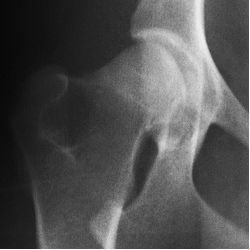

當前主流的骨關節保健品主要有葡萄糖胺(glucosamine)、軟骨素(chondroitin),以及有機硫同化物(methyl-sulfonyl-methane,即MSM)等。葡萄糖胺和軟骨素在骨關節處形成蛋白聚糖,吸收水分和體液,使關節運動時得到潤滑,而MSM則是止痛劑。這些都僅僅是緩解症狀,很難治本。美國UCLA骨科專家臨床研究表明,一般葡萄糖胺要四、五年才能修復軟骨;而以Kolla2(Ⅱ型骨膠質)為主方,輔以上葡萄糖胺、MSM等,則大大縮短消除關節疼痛和修復軟骨的時間。研究證明服用Kolla2(Ⅱ型骨膠質)六周后,患有髖關節發育異常的犬科動物恢復了正常運動功能,隨後的X-射線檢查表明其髖關節軟骨恢復正常。